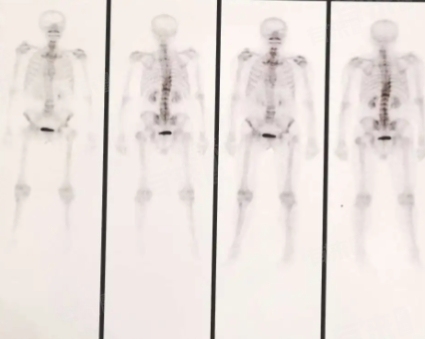

骨扫描是利用放射性核素进行的检查,确实存在一定辐射。但单次骨扫描所接受的辐射剂量通常在人体可承受范围内。检查后,放射性物质会随时间逐渐代谢排出体外。不过对于特殊人群如孕妇、儿童等,若非必要应谨慎选用,以防潜在辐射危害。

- 骨扫描是一种利用放射性核素进行的检查,常用的放射性药物如锝-99m标记的化合物。在进行骨扫描后,这些放射性药物会随着身体的代谢过程逐渐排出体外。一般来说,大部分放射性药物在检查后的24-48小时内会通过尿液排出大部分,但是完全从体内清除可能需要几天的时间。